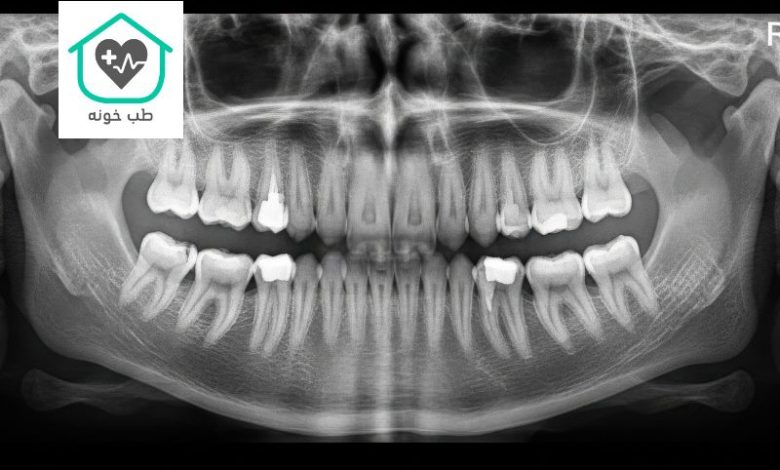

عکس او پی جی دندان (مخفف Orthopantomogram) را میتوان به عنوان عکس پانورامای ۳۶۰ درجه از کل دهان شما تشبیه کرد. این تصویر دو بعدی، یک نمای کلی و پیوسته از تمام دندانهای بالا و پایین، استخوانهای فک، مفاصل گیجگاهی-فکی (TMJ) و حتی بخشهایی از سینوسها را در یک قاب واحد نشان میدهد. به همین دلیل است که بسیاری از مردم به آن عکس دندان کامل انسان میگویند. این عکس، اولین و مهمترین نقشه راه برای دندانپزشک شما در یک معاینه جامع است.

کاربردهای اصلی عکس OPG:

- چکاپ کامل دندانپزشکی؛ اولین قدم در یک معاینه جامع برای بیماران جدید

- بررسی دندانهای عقل؛ بهترین ابزار برای دیدن موقعیت، زاویه و وضعیت دندانهای عقل نهفته

- ارزیابی کلی برای درمانهای پروتزی مانند برنامهریزی برای ساخت یک پروتز ثابت دندان

- بررسی مشکلات مفصل فک (TMJ) مانند درد، صدا یا محدودیت در باز کردن دهان

- تشخیص شکستگیهای فک ناشی از ضربه و حوادث

عکس او پی جی دندان یک ابزار تشخیصی فوقالعاده کارآمد است که با یک بار تابش اشعه، اطلاعات بسیار زیادی را در اختیار دندانپزشک قرار میدهد.